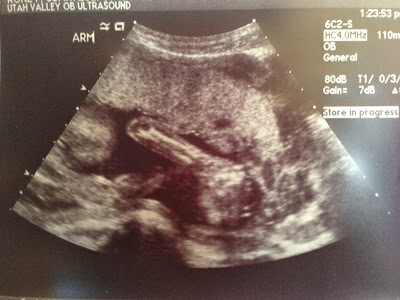

Look how beautiful my little man is! And I'll be the first one to tell you how much I didn't get the big deal about these ultrasounds. "They're really weird black and white pictures of what resembles a baby," Id' think. NOW I get it!

| I love this little face of his! I cant wait to see it! |

| Yep, that is DEFINITELY a boy! |

| Yummy arms for me to squeeze and kiss all over! |

| and don't forget those cute legs and feet!! I can't wait for him to be here in my arms! |